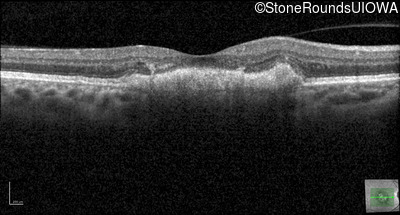

Age at visit: 39 years

Diagnosis & molecular findings

Disease Gene Allele 1 variant(s) Allele 2 variant(s) Inheritance mode

Pattern Dystrophy PRPH2 Gly167Asp GGC>GAC   AD